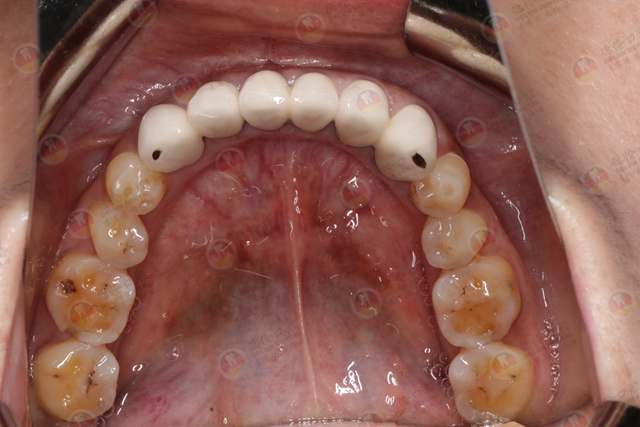

烤瓷牙失败案例